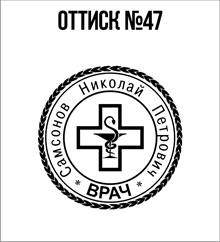

- Первое – это огромный выбор клише, то есть изображений будущей печати. Посмотрите, пожалуйста, чуть выше у нас на данной странице сайта имеется галерея изображений. Вы можете выбрать любое понравившееся Вам и сделать заказ;